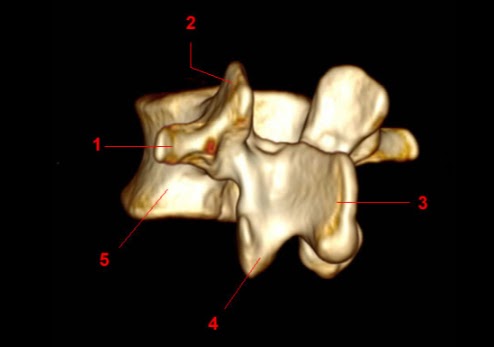

Vista oblicua cuerpo vértebra lumbar en Reconstrucción Multiplanar 3D por TC:

1.- Apófisis Transversa

2.- Proceso (carilla) articular superior

3.- Apófisis espinosa

4.- Proceso (carilla) articular inferior

5.- Cuerpo vertebral